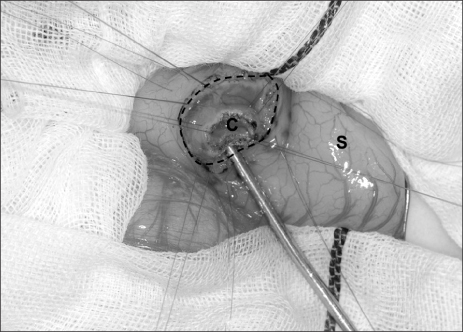

4] and the lumen was hypoechoic. A gastrografin swallow with upper gastrointestinal study demonstrated a mass obstructing the pyloric orifice. A small quantity of gastrografin passed around the perimeter of the lesion and entered the duodenum. Following fluid resuscitation and stabilization, an enteral digestive (ED) tube was inserted on day 7. Magnetic resonance cholangiopancreatography (MRCP) demonstrated that the cystic lesion was located in the pyloric orifice. However, T2-weighted sequences, obtained in the coronal plane did not reveal whether the fluid content of the lesion communicated with the bile duct or not. On day 22, body weight was 2,815 g and an operative exploration was undertaken. A laparotomy was performed through a transverse upper abdominal incision. No cyst was identified, but, an elastic mass was palpable at the pyloric orifice. Intraoperative endoscopy revealed a submucosal gastric lesion approximately 15 mm in size arising from the anterior and inferior surfaces of the pylorus (

Fig. 2). Intraoperative cholangiography documented no communication between the cystic lesion and the bile or pancreatic ducts. Gastrotomy was performed transversally over the antrum just proximal to the cyst, and the cyst was delivered in toto through the incision. The cyst was incised (

Fig. 3Intraoperative findings of the duplication cyst. A transverse gastrotomy was performed to approach the cyst from inside the stomach. The cyst was incised and a mucosectomy was performed via a gastrotomy. C, cyst; S, stomach; broken line, transverse gastrotomy.